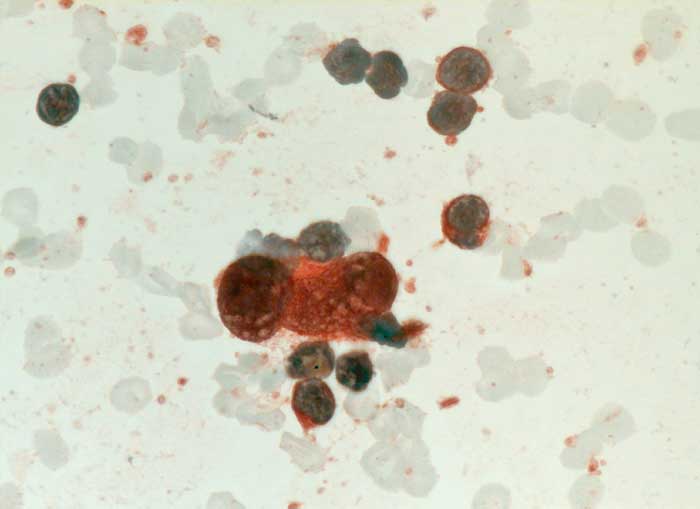

l/ Hodgkin Lymphom

Hodgkin Lymphom

Reed-Sternberg Zellen und Hodgkin Zellen des klassischen Hodgkin Lymphoms (lymphozytenreich, noduläre Sklerose, Mischzelltyp, lymphozytenarm) sind positiv für CD15 und CD30. Die Tumorzellen des nodulären lymphozytenprädominanten Subtyps hingegen sind positiv für CD20 und CD45.